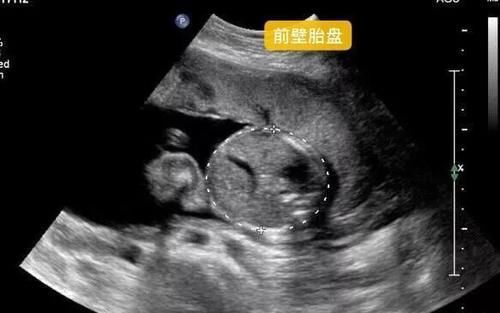

妊娠21週目エコー写真 胎動の様子 胎児の大きさや体重 性別 妊娠中期 All About